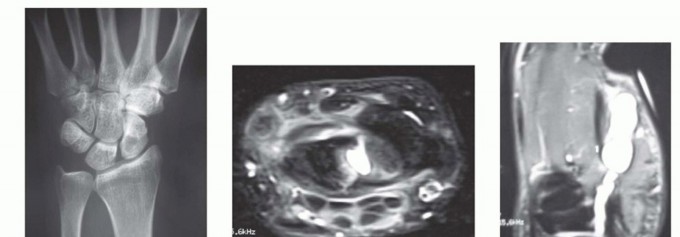

FIG 3 • A. Radiograph showing an intraosseous ganglion cyst within the scaphoid. B. MRI of a dorsal wrist ganglion cyst extending into the scapholunate joint. C. MRI of a ganglion cyst arising from the scaphotrapezial joint and extending into the thenar eminence. D. MRI of a ganglion cyst in the snuffbox but arising from the dorsal scapholunate ligament. MRI can also be used to better localize the site of origin as part of preoperative planning in ganglion cysts that occur in atypical locations (FIG 3C,D).Ultrasound can also be used to diagnose ganglion cysts, but this test is examiner dependent and lesssensitive and specific than MRI.Computed tomography (CT) scans are generally obtained only for preoperative planning to better localize and evaluate the bony architecture of intraosseous ganglion cysts.